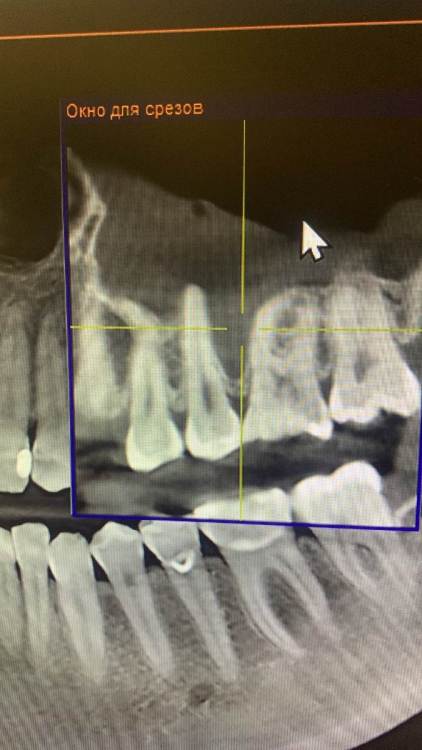

KOCTb Опубликовано 1 января, 2024 Поделиться Опубликовано 1 января, 2024 Здравствуйте коллеги. Может кто-то подскажет полезного. Пациентка. Лет 6 назад пришла с симптоматикой пульпита во втором секторе. На некоторых зубах были пломбы, без криминала. Зубы были проверены на витальность. Все живые. Пальпаторно передняя стенка ВП давала лёгкую чувствительность. Сделали КТ. Апикальных изменений не выявлено, а в пазухе слева признаки гайморита. Заполнена была бальше чем наполовину. Отправил к ЛОРу. Пролечили. Анатомическое строение не очень понравилось. С тех пор каждую зиму у неё обострение ВЧ синусита слева. Иногда даже два раза бывает. Каждый раз ЛОР в направляет к стоматологу и говорит, что гайморит одонтогенгый. Врачи рентгенологи в описании иногда там находят одонтогенгую кисту… Года два назад пациентка сходила поменяла все пломбы, на всякий пожарный. Со слов зубы все были витальные при лечении. Ну и собсвенно опять ВЧ синусит. Смущает анатомическое строение между 25 и 26 зубом. Не может ли там через периодонтальную щель «сифонить» ? Говорит между зубами иногда какой-то дополнительный дискомфорт есть. Ссылка на комментарий

Irouil Опубликовано 3 января, 2024 Поделиться Опубликовано 3 января, 2024 Было бы чему "сифонить" - зондировался бы свищ через пародонт, было бы разрушение межзубной перегородки. Имхо, это невозможно Одонтогенную причину пока в упор не вижу Ссылка на комментарий

KOCTb Опубликовано 15 января, 2024 Автор Поделиться Опубликовано 15 января, 2024 19 часов назад, Astronaft сказал: Здравствуйте. 6 лет назад: подробнее про симптомы пульпита? как полечили гайморит и чего добились? Анатомия действительно интересная. Интуитивно, или естественная впадина которая способствует застою либо проблемы в соустье вызывают застой и кислотный секрет лизирует самое слабое место. Опять же интуитивно, пациентке приказать зубы не трогать, не ходить выискивать проблемы. Очень подробно расспросить анамнез, в том числе что помогает, что запускает синусит. Если соустье открыто то я бы рекомендовал регулярно промывать физраствором с ЭДТА и выждать. Здравствуйте. Ну как обычно пульпитная симптоматика при ВЧ синусите. Разлитые периодические боли в верхнем секторе, с непонятной локализацией. Пальпаторно передняя стенка ВЧ пазухи давала болезненность. От 25 до 27 зуба. На КТ зубов затенение в ВЧ пазухе. Отправил тогда к ЛОРу. Подробности лечения у ЛОР врача тогда не знаю. Синуситы в холодное время года. Соустье пародонтальным зондом не выявлено. Носо-ротовая проба также отрицательная. Но тут и понятно если и есть ход, то крайне мизерный. Там слизистой завалено всё. Ссылка на комментарий